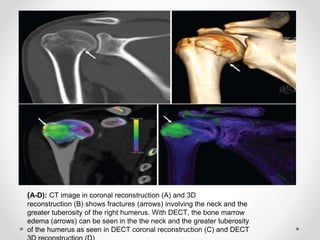

(A-D): CT image in coronal reconstruction (A) and 3D

reconstruction (B) shows fractures (arrows) involving the neck and the

greater tuberosity of the right humerus. With DECT, the bone marrow

edema (arrows) can be seen in the the neck and the greater tuberosity

of the humerus as seen in DECT coronal reconstruction (C) and DECT

Using DECT, the artefacts from metal can be significantly reduced to almost nil. As